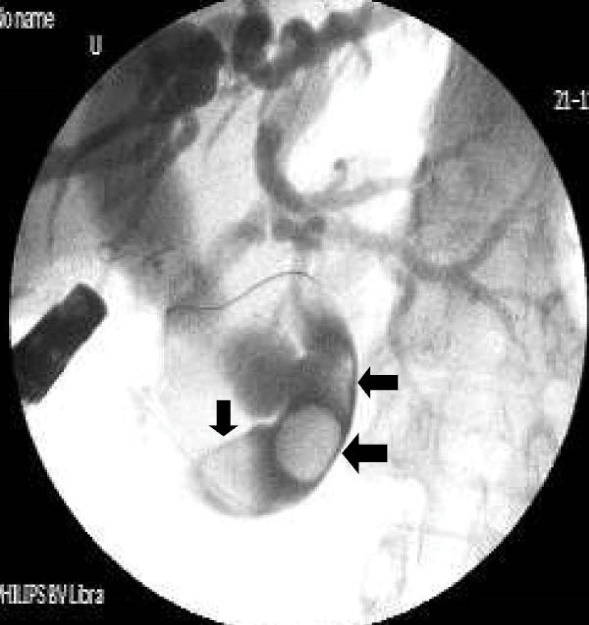

Table 2 shows detailed cholangiographic information about all patients. The indication of ERCP was recurrent acute cholangitis associated with bile duct dilatation in 20 patients and abdominal pain associated with elevated liver enzymes and dilatation of bile ducts in 9 patients. CBD cannulation was successful in all patients and we did not use needle knife papillotomy for cannulation in any patients. We could not pass the duodenoscope to the second portion of the duodenum because of apical stenosis in 5 patients; we used a gastroscope (because it is thinner than a duodenoscope) to visualize the second and third portion of the duodenum in those patients and confirmed that the opening site of CBD was located above the apical stenosis site. CBD cannulation and therapeutic intervention were performed with the duodenoscope in all patients. Cholangiography showed diffuse dilatation of the extrahepatic bile duct (median 17 mm: range 12 to 40 mm in diameter,) and intrahepatic bile ducts in all patients. The dilated CBD showed tapered narrowing and a hook-shaped distal end in all patients (Figure 4). Twenty-six out of 29 (89%) patients had bile stone (Figure 5) and three (10%) patients had sludge in bile ducts. We did not perform sphincterotomy in any patients because there was not enough incision distance. After cholangiography, we dilated the ectopic opening orifice with a pyloric dilatation balloon (range 12–18 mm in diameter) in all patients for stone and sludge extraction and for free biliary drainage. Complete stone extraction was achieved in 7 out of 26 (27%) patients with bile duct stone. In 19 patients whose stone could not be retrieved because of acute angulation, tapered narrowing and a hook-shaped distal end of CBD and un-effective pull back of balloon catheter for extraction of stones, a nasobiliary drain (n = 12 patients) or stent (n = 7) was placed for prevention of cholangitis. We did not observe any complications such as bleeding, perforation and acute pancreatitis related to ERCP and balloon dilatation. The pancreatic ducts were opacified in 5 out of 29(17%) patients via separate opening site and there was not any communication between the pancreatic canal and bile ducts. We did not opacify the pancreatic canal in the remaining 24 patients because our primary aim was to perform biliary therapeutic intervention.

Patients with ectopic opening of the CBD usually have clinical symptoms and signs of biliary tract diseases. Dilatation of intrahepatic and extrahepatic bile ducts, a hook-shaped configuration of the distal end of the CBD and biliary stones were the most common ERCP findings in this anomaly. The most common clinical presentations in these patients are bile duct stones, recurrent cholangitis, obstructive jaundice and abnormal liver function tests.1–6 Normal sphincteric musculature is absent around the entrance of accessory bile ducts into the gastrointestinal tract.14,18 In our case series, we found diffuse dilatation in both extrahepatic and intrahepatic bile ducts in all patients. We did not identify any stricture preventing biliary drainage on cholangiography in any patients. Because of the presence of diffuse dilatation in bile ducts, we can speculate that in addition to acute angulation of the distal end of the CBD, sphincter dysfunction may impede normal bile stream and cause chronic bile stasis, bile duct dilatation and formation of biliary sludge and bile stone. Manometric measurement may yield more accurate information about sphincter functions in these patients.